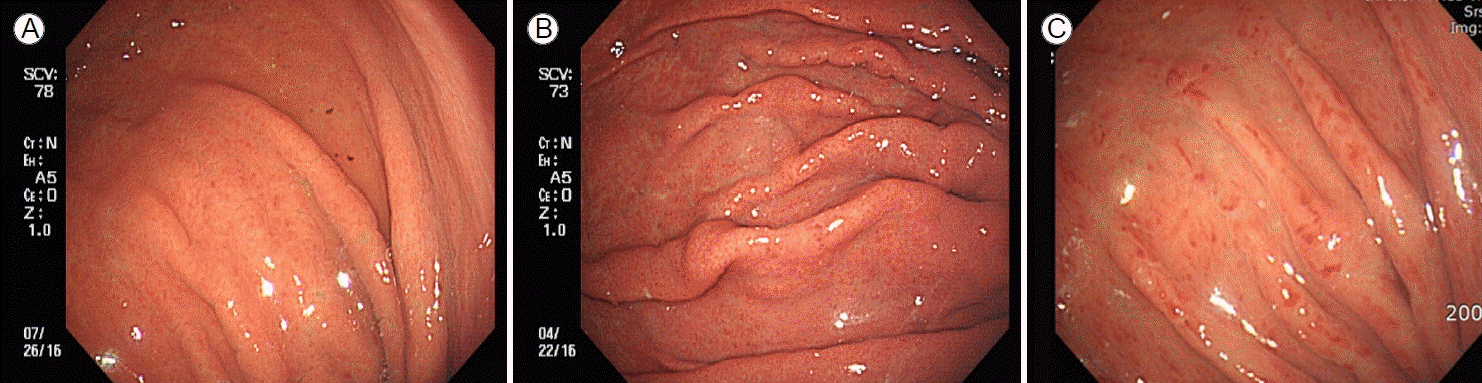

발적성 위염의 내시경 소견을 보인 환자에게 관찰된 발적 주위에서 급속 요소분해효소 검사(Campylobacter-like organism test) (CLO® test; Kimberly-Clark, Roswell, NM, USA)를 시행하여 양성 또는 음성을 판정하였다. 시드니 분류에서 발적(erythema)은 주변 점막에 비해 좀 더 어둡게 붉은 점막이 불균일하게 군데군데(patchy) 구별되어 있는 영역으로 정의된다. 또한 발적만 있을 경우에는 발적성 위염, 발적과 삼출물이 동시에 있을 경우에는 발적성/삼출성 위염이라고 표시한다. 본 연구에서는 발적과 삼출물이 동시에 있는 발적성/삼출성 위염은 제외하고 발적만 있는 발적성 위염만을 대상으로 하였다. 발적성 위염의 중증도는 발적이 약간이지만 명백한 변화(minimal but obvious change)를 보일 때 경도, 식별 가능한 반상의 변색(patchy discolouration)을 보일 때 중등도, 짙은 붉은색(beefy-red)의 변화를 보일 때 중증으로 분류하였다(Fig. 1) [9]. 그리고 헬리코박터 파일로리 양성은 급속 요소 분해효소 검사 양성으로 정의하였다.

Figure 1.

Endoscopic findings of erythematous gastritis. (A) Mild erythematous gastritis is characterized by minimal erythema but the presence of obvious change. (B) Moderate erythematous gastritis is characterized by conspicuous patchy discoloration. (C) Severe erythematous gastritis is characterized by a color change that is beefy-red in intensity.